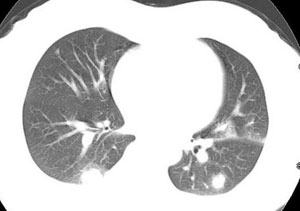

女性,30岁。

病史为胸痛20多天,无畏寒发热,无消瘦,无咳嗽咳痰。总之症状很逍遥。

临床以胸痛待查收住入院。

双肺野可见散在大小不等结节及肿块影,内密度不均匀,边缘部分清,部分欠清,纵隔未见明显肿大淋巴结.右侧胸腔少理积液.结合临床,考虑韦格肉芽肿可能吧,巨淋巴增生,结节病,特殊感染都要考虑.转移瘤临床不象.

本病例特点如下:

1.青年女性,以胸痛20多天就诊,无呼吸道及感染临床症状体征,无原发肿瘤病史;

2.肺ct表现为两肺多发大小不等结节影,大结节位于肺尖部,小结节多位于肺外带胸膜下,大结节内可见支气管充气征,周围可见月晕征(指在结节状或肉芽肿样病灶周围呈环形磨玻璃影),右肺门及腔静脉后可见小淋巴结,右侧胸腔内少量液体。

两肺散在分布大小不等的肿块及结节影,边缘毛糙,有分叶、毛刺,病灶密度不均匀,可见支气管充气相与空泡征。病变大多位于胸膜下,可见胸膜凹陷及胸腔积液。气管腔静脉间可见小结节影。